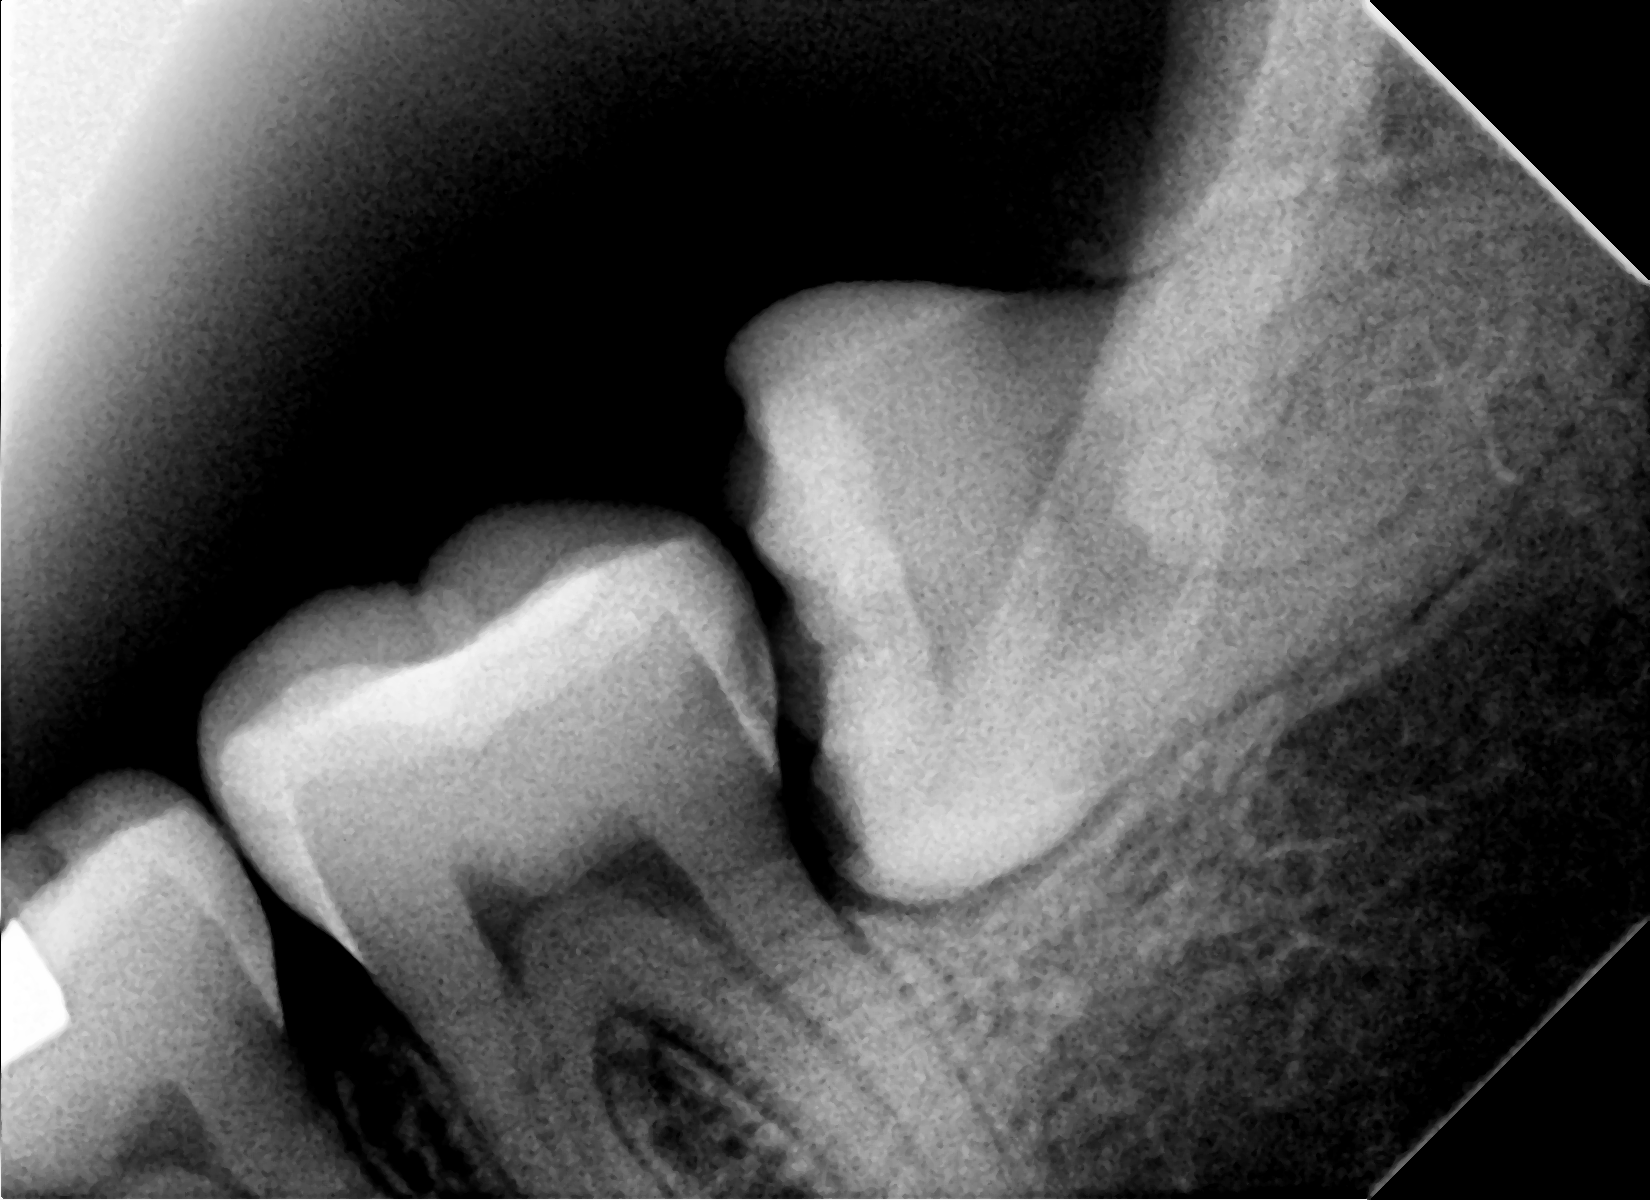

Paciente masculino 65 años, presenta Periodontitis Crónica Generalizada, se realiza extracciones totales de piezas superiores, se colocan 4 implantes dentales para sobredentadura, 4 meses después paciente disfruta de una nueva y renovada sonrisa, sin necesidad de retirársela, ni de preocupaciones de que la prótesis se le desplace al comer o hablar.